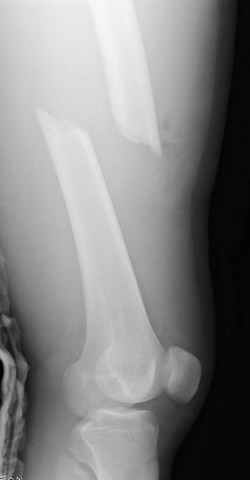

больному 42, автоавария, политравма, открытая черепномозговая травма, безсознании, открытый перелом бедра, размозжение мягких тканей, дефект кожи на передней поверхности бедра около 13 см2 от ожога, компартмент синдром.

По поводу открытого перелома больной ургентно взят на ретроградное интрамедулярное штифтование, после рутинного дебрайдмента и фасциотомии на бедре и на голени.

перелом бедра